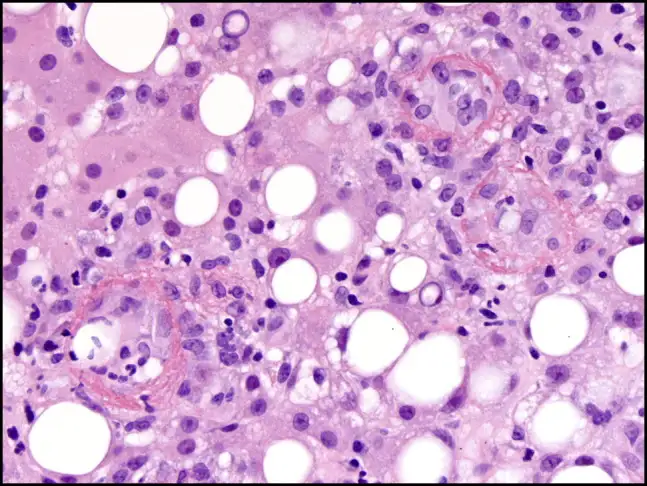

然而,Q热真正令人恐惧的并非急性期,而是它的慢性化。大约1%到5%的急性感染者在数月甚至数年后会发展为慢性Q热,这是一种完全不同的疾病。病原体在体内潜伏,等待机会,最终在一些特定的部位——通常是心脏瓣膜——建立慢性感染。慢性Q热心内膜炎是最常见也最致命的表现。它发展缓慢、隐匿,患者可能只是感到疲劳、体重下降、低热、关节痛,这些症状被归咎于其他原因,直到心脏瓣膜被严重破坏。

慢性Q热心内膜炎的病死率令人震惊:未经治疗的患者,病死率高达25%到60%。即使接受治疗,患者也需要服用抗生素长达18个月到数年,甚至终身。治疗方案通常是多西环素联合羟氯喹,后者可以碱化吞噬溶酶体,削弱细菌的酸性生存优势。这种治疗可以显著降低病死率,但副作用也不容忽视——长期服用多西环素可能导致光敏性皮疹和牙齿变色,羟氯喹则有视网膜毒性的风险。